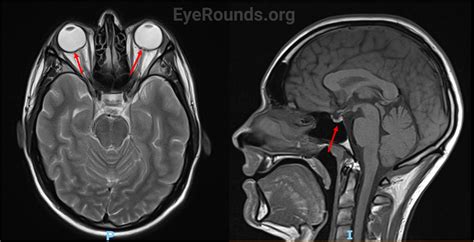

• Neurological Imaging: It is used to detect brain tumors, strokes, and other neurological conditions. The detailed images help neurologists identify abnormalities and plan treatment strategies.

Brain Tumors Detects abnormalities in the brain, including tumors, cysts, and other lesions.